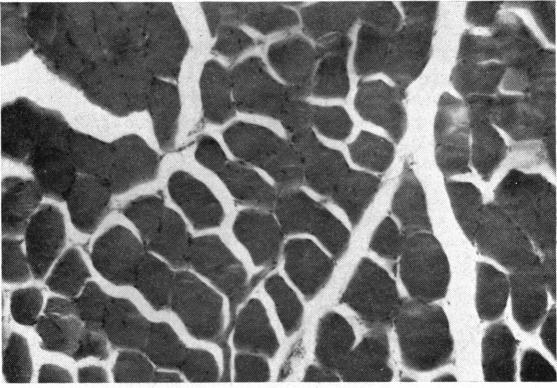

PROGRESSIVE MUSCULAR DYSTROPHY INVOLVING THE EXTRA-OCULAR MUSCLES WITH NOTES CONCERNING OPERATIVE TREATMENT OF THE ASSOCIATED DIVERGENT SQUINT.

Br J Ophthalmol. 1965 Feb;49(2):102-5. doi: 10.1136/bjo.49.2.102.